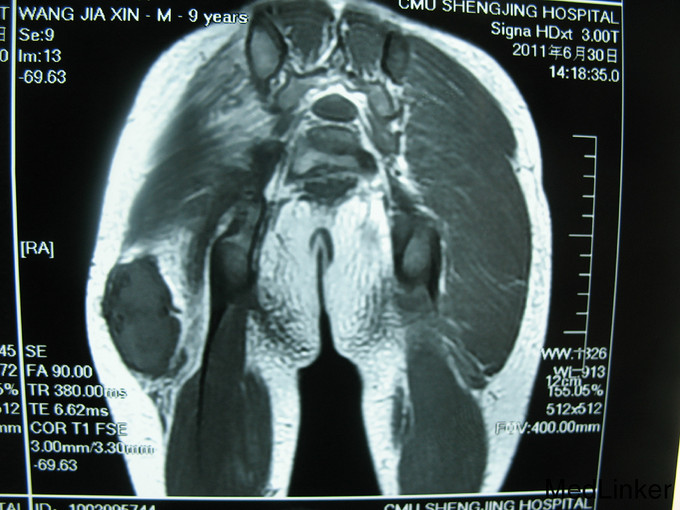

右臀部手术区可见15cm长的手术瘢痕,瘢痕下可 及硬韧肿物大小约10x7cm,边界不清,活动度差。

侵袭性纤维瘤病是一种不明原因、不发生转移的成纤维细胞性瘤样肿物。起源于肢体和韧带的肌筋膜结构,累及骨骼肌腱膜和筋膜,并对周围组织产生压迫。病变很易局部复发,并呈侵袭性生长,最常见于青年人的肩胛带、股部及臀部。侵袭性纤维瘤术后复发几率高,对周围组织侵袭性强。本例患者给予扩大切除术后随诊至今未发现复发病灶。